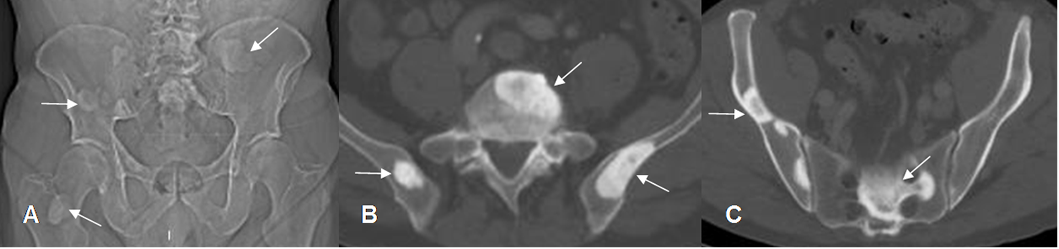

Fig 150. Metástasis blásticas.

A: Rx AP, B y C: TAC axial. Múltiples lesiones densas en los huesos iliacos, columna y fémur derecho, por metástasis blásticas de neoplasia pulmonar.